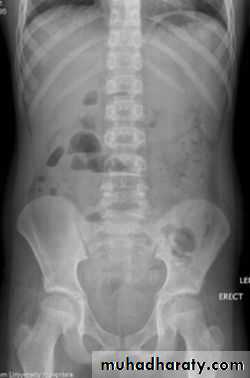

Positioning

• Supine AP

• Erect AP

• Lateral decubitus

The main purpose of horizontal beam films is to detect air-fluid levels and free intraperitoneal air